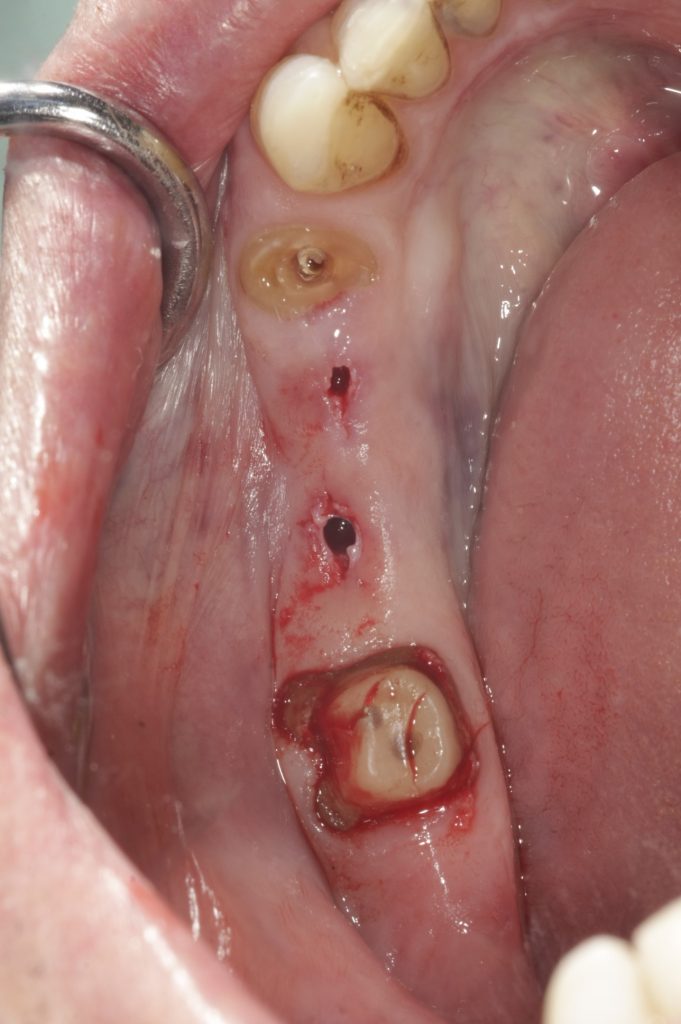

Autores: PRÓLOGO Asimismo, desde el punto de vista pedagógico, el profesional nobel en la materia tiene a su alcance la posibilidad de corregir cualquier posición implantaría en el ordenador, planear los provisionales y plasmarlos en la bio réplica antes de tocar al paciente a operar. Todos estos razonamientos nos llevan a presentar un caso de condiciones muy favorables para poner en práctica estos métodos como primer acercamiento a una Odontología Digital de alta calidad, con medios informáticos, que ya están presentes en la profesión de hoy en día, y será la protagonista única del futuro. Por otro lado, después de numerosos estudios que nos llevan a plantear el “gap” entre implante y pilar(abuttment), como principal responsable de la periimplantitis dado que la microbiota presente en el mismo es imposible de limpiar y en su presencia la cortical ósea reacciona reabsorbiéndose, nos ha llevado a utilizar implantes monobloc ya que los ejes implantarios y protéticos coincidían, y nos permitían su uso. Además, el circonio, ha mostrado a la luz de estudios muy recientes, una preservación y adhesión de los tejidos blandos superiores al titanio, tanto en su tratamiento de superficie de la rosca como a nivel gingival. DESARROLLO Paciente varón de 68 años, con antecedentes de radio/quimioterapia cinco años antes, con Rehabilitación Oral de los cuatro cuadrantes, con una Oclusión Mutuamente Compartida conservada, (REF.8) la que fracasa en el cuadrante 4, 19 años después. El mismo presentaba un puente de porcelana sobre circonio con pilares en 44 y 47, reemplazando el edentulismo de 45 y 46. Se produce la fractura del PM del 44, y ante una endodoncia antigua y corta, se decide implantar las zonas edéntulas, conservando temporariamente los pilares, hasta producida la oseointegración, para entonces también exodonciar el 44. DIAGNÓSTICO Tomamos impresiones del maxilar antagonista, Arco Facial Estático y realizamos montaje del mismo mediante la sistemática ARTEX. Producimos la relajación del músculo Pterigoideo Externo, para obtener la ORC (Oclusión en Relación Céntrica) mediante el método de Laminillas de Long, basado en el concepto de INERVACIÓN RECÍPROCA. Esto nos permitirá montar el maxilar inferior, tanto en su forma de: La primera para practicar la cirugía guiada y comprobar su eficacia, y el modelo de yeso para ser escaneado y confeccionar la GUÍA QUIRÚRGICA. La Biorréplica la obtenemos transformando los archivos DICOM que nos da el CBCT en archivos STL, y a partir de ellos, mediante una tecnología de PROTOTIPADO RÁPIDO, la obtención de un objeto físico en 3D a través de la aglutinación selectiva de una sucesión de capas de polvo. Procedemos a montar la biorrèplica y el modelo de yeso del caso. Podemos verificar la exactitud de las medidas del hueso residual en la bio réplica y compararlas con el scanner. Arrojando un resultado de 8,5 mm de cortical externa a cortical externa. Pudiendo también medir la distancia hasta el dentario. y comparar gracias a la ventana lateral de la biorréplica Dándonos 22mm de distancia. Con lo cual deducimos que implantes de 4,1mm por 12 mm serán perfectamente rodeados de hueso. Medimos también la distancia desde oclusal del antagonista, hasta el hueso desnudo. Lo mismo que, mediante la utilización de la guía radiológica, con un material radiolúcido colocado en gingival de la misma, podemos medir la altura de la encía. Con lo cual podemos calcular la altura del pilar. Es entonces cuando con el programa COC Diagnostix se realiza la programación final: Obteniendo no solo la ubicación, largo, ancho y ángulo de los implantes sino también los provisionales mediante CAD CAM. Ya entonces podemos hacer la práctica quirúrgica en la bio réplica, mediante la guía quirúrgica, instalando los implantes de prueba que no serán los de circonio, ya que la casa no cuenta con ellos, pero si otros de las mismas dimensiones. TRATAMIENTO Entramos ya en la cirugía propiamente dicha. Antisepsia de la zona a operar y zonas anexas. Comprobación del perfecto ajuste e inmovilidad de la G.Q. en boca durante la cirugía. Marcado de la encía y perforación de la cortical. Visión a través de la Guía de la mínima intervención anterior. Comprobación sin Guía. Incisión mínima mesio distal, para apartar y conservar encía queratinizada. Secuencia de drills, perforando a profundidad requerida Observación del Mínimo Trauma Implantes Strauman de Zirconio Monoblock en blíster y montádo en contrángulo reductor. Instalación controlando torque con contrángulo reductor. Comprobación clínica. Comprobación Radiográfica y con Guía. Toma de impresiones, y armado de modelos con técnicas de pasividad protética. Montaje. Resultado de las provisionales ejecutadas por CAD CAM Al no estar conformes con el resultado decidimos desechar dichas provisorias y optar por repetirlas. Nuevas provisorias realizadas mediante encerado convencional. Estado de los tejidos blandos. Provisorias en boca. Oclusión de Estímulo Inmediato. Ref.10: Carga inmediata .Alberto y Diego Bechelli. Comprobación mediante CBCT post operatorio Componentes del equipo (En la próxima presentación, mostraremos las coronas definitivas de porcelana sobre circonio, y la desoclusión provocada por una OCLUSIÓN MUTUAMENTE COMPARTIDA, sobre estos implantes y otros seis mas) REFERENCIAS

FIG: 1-2-3-4

Clinicamente es una boca rehabilitada y conservada en su totalidad, salvo este cuadrante que nos ocupa.

Realizamos previamente una Rx periapical Dígora (radiovisiografía) y un CBCT (TAC de haz de cono) con férula radiológica, marcando ambas raíces del 46 y la raíz del 45.

FIG: 21-22-23-24-25-26

Fig. 21

Fig. 22

Fig. 23

Fig. 24

Fig. 25

Fig. 26

FIG:47-48-49

FIG:50-51-52-53-54

Fig. 50

Fig. 51

Fig. 52

Fig. 53

Fig. 54